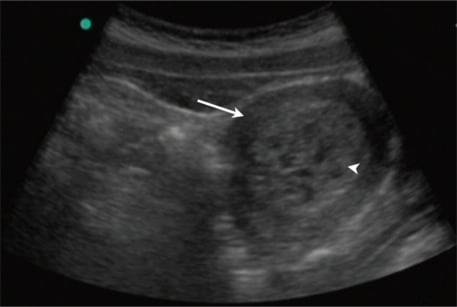

Fig 1 - High magnification image of choriocarcinoma. The cell population consists of cytotrophoblasts and syncytiotrophoblastics

High magnification image of choriocarcinoma. The cell population consists of cytotrophoblasts and syncytiotrophoblastics